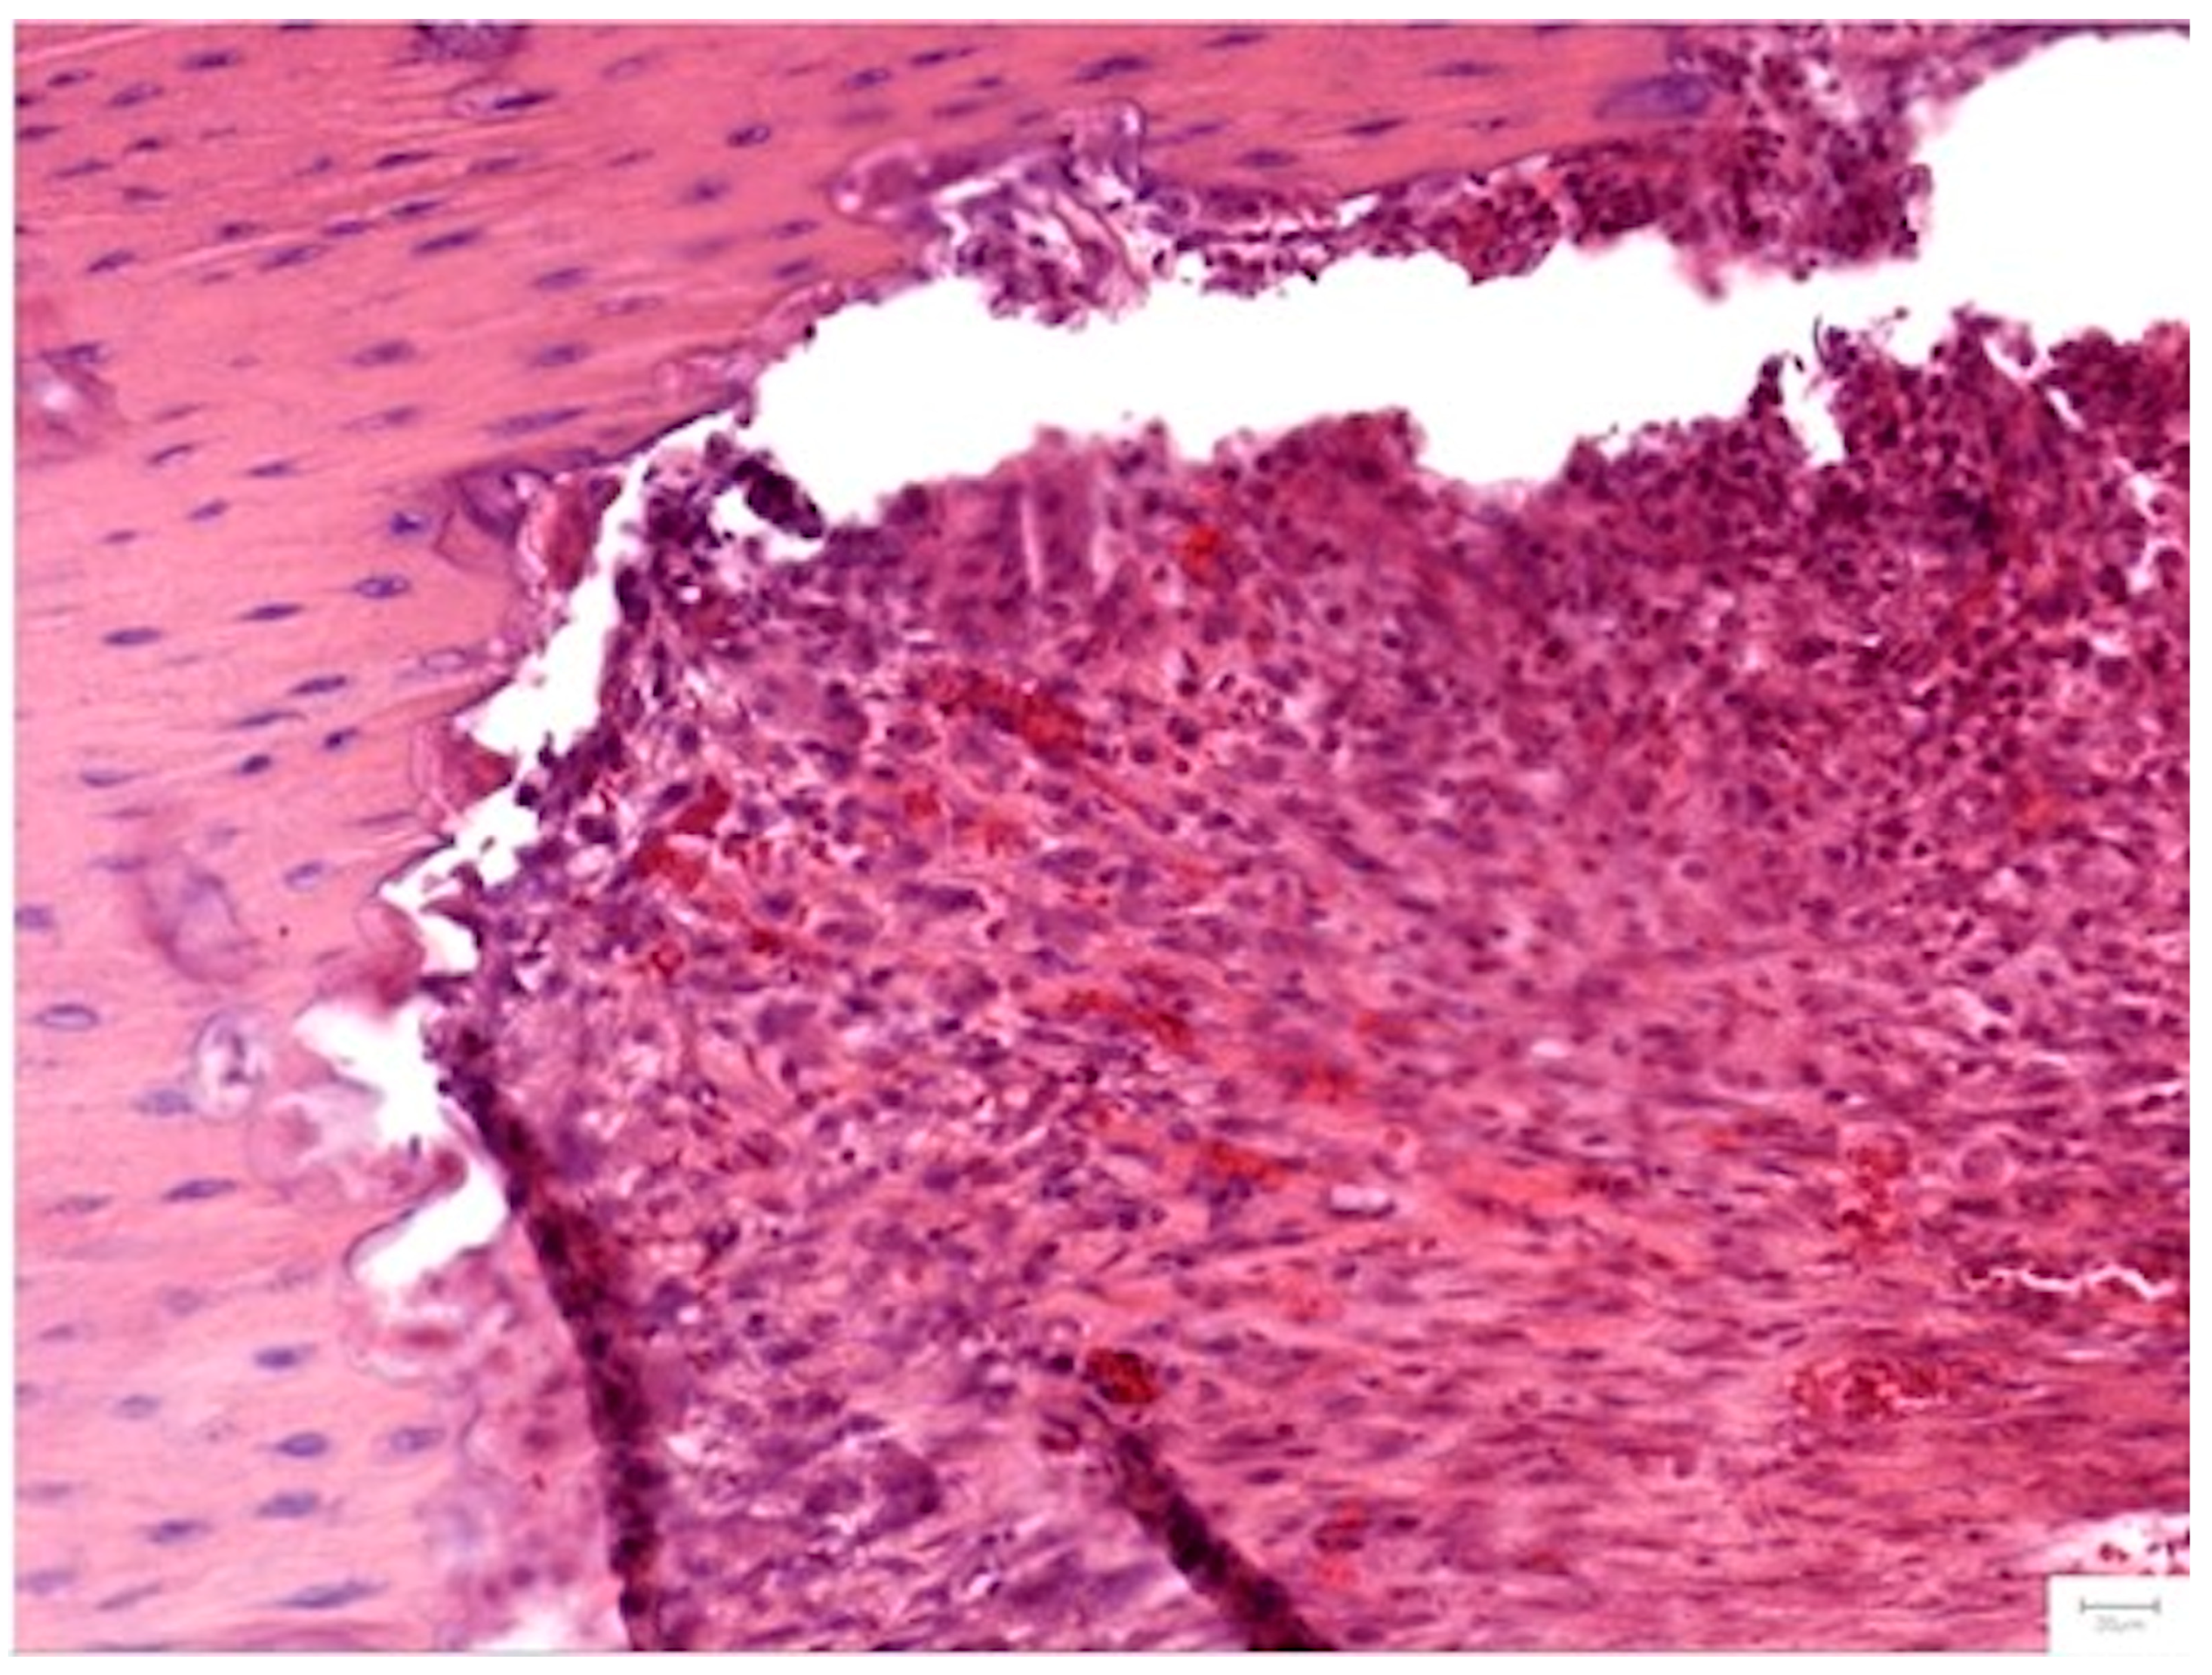

Cellular Response and Vascularization

The cellular dynamics varied by treatment. Group II (HS/Vit. D3) showed significantly higher scores for osteoblasts (p = 0.045 at 1 month) and osteocytes (p = 0.025) compared to Group III, indicative of an intense early metabolic burst. However, Group III (NS/Vit. D3-2.5) exhibited superior vascularization at the 1-month mark (p = 0.045), with capillaries penetrating the center of the graft in all samples (Figure 12). This early angiogenesis likely supported the subsequent maturation of the bone matrix observed at 2 months.

Figure 12.

Vascularization in Group III (NS/Vit. D2-2.5) at 1 month (H&E, 20×). The defect shows organized and centrally penetrating capillaries, consistent with the enhanced angiogenic response. Dense connective tissue surrounds the newly formed vessels.